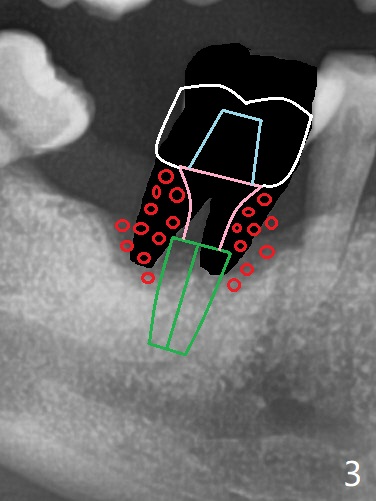

69岁男拔除左上5后右下6疼痛,要求拔除,骨质吸收严重,牙龈厚(图一:双箭头),其实后者是好事,血供好,植牙可以种植浅些(图二),周围放置骨粉(图三:红圆圈)。拍摄根尖片:近中牙槽窝种植与中隔种植,植体长度有优势(图五,四)。